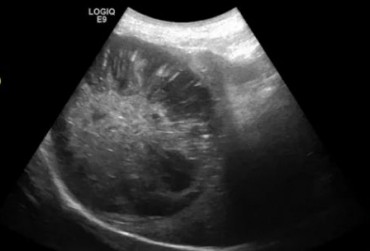

Pies, owczarek szetlandzki 6l. Mukocele. - 2

24 czerwca 2019

Wojciech Atamaniuk

Pies, owczarek szetlandzki 6l. Mukocele. - 1